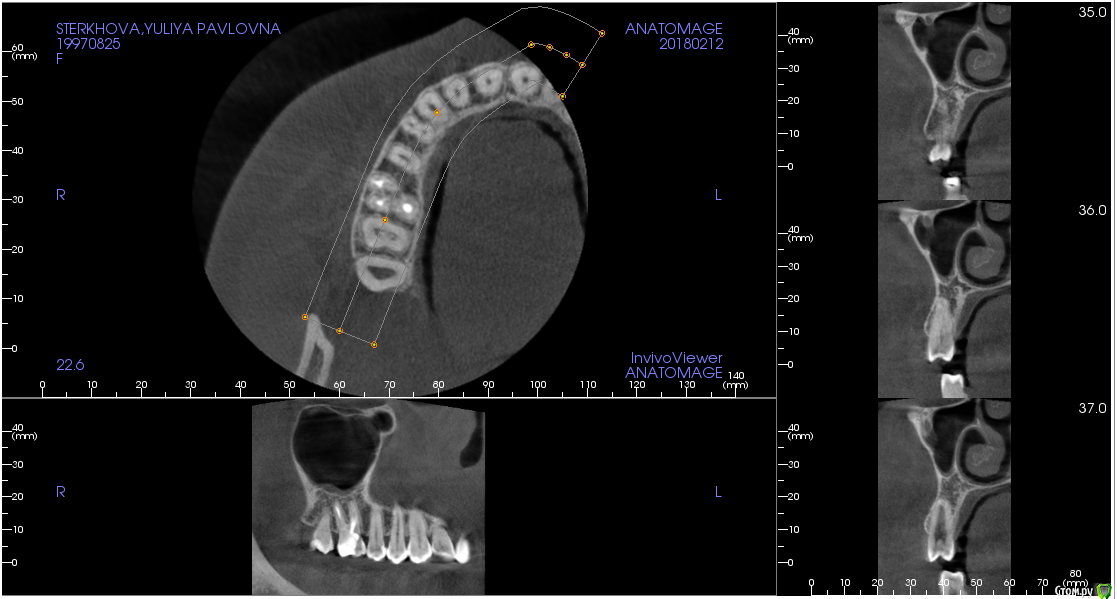

Стерхова Юлия Опубликовано 1 марта, 2018 Автор Поделиться Опубликовано 1 марта, 2018 (изменено) Снова здравствуйте! Так зуб и не хочет оставить меня в покое. С момента последнего сообщения был сделан 3д снимок (прилагаю ссылку с ним на файлообменник: https://ru.files.fm/u/u275ad6j),на котором врач нашёл недепульпированный 4 канал. Неделю назад этот канал прочистили (оказался пустым), поставили временную пломбу, но боль не исчезла, только усилилась. На следующем приеме врач сделал прицельный снимок и нашёл незапломбированный до конца третий канал, а также хроническое воспаление. Было принято решение перелечить все оставшиеся три канала, чтобы не допустить повторения воспалительного процесса. При этом даже через двойную дозу анестезии я чувствовала при лечении сильнейшую боль. Так же была по итогу поставлена временная пломба, выписали антибиотик и обезболивающее. Прошло двое суток после лечения, сильная боль во всем зубе продолжает беспокоить - сильней во много раз, чем до лечения. Нормально ли это? Или все-таки даже и это лечение не помогает? Возможно ли, что дело дойдет до удаления? Изменено 1 марта, 2018 пользователем Стерхова Юлия Ссылка на комментарий

red_butler Опубликовано 1 марта, 2018 Поделиться Опубликовано 1 марта, 2018 прилагаю ссылку с ним на файлообменниквыкладывайте срезы Кт, весь архив мало кто захочет, или сможет скачать.А лучше сделать новый прицельный снимок Ссылка на комментарий

Стерхова Юлия Опубликовано 1 апреля, 2018 Автор Поделиться Опубликовано 1 апреля, 2018 Выкладываю старые срезы с опозданием(Я уже не знаю, как быть. Подскажите, пожалуйста! В общем, каналы уже месяц перелечиваются под микроскопом, диагноз - периодонтит. Примерно каждую неделю все прочищается и закладывается под временную пломбу лекарство, но результата нет - сохраняется боль в ночное время и во время очищения каналов. В гайморовой гранулёма. Несмотря на все это, хирург выступает категорически против удаления, терапевт тоже, на 7.04 запланирована пломбировка. Но на этой неделе я обратилась к ЛОРу, он поставил диагноз тонзиллит (на фоне инфицирования зуба), гайморит (из-за гранулёмы), а также нашел остаток пломбировочного материала в пазухе. Он - за удаление. Хирург наличие пломбы в пазухе отрицает. Кому верить в данной ситуации? Когда лучше сделать новое КТ: до или после пломбировки? И стоит ли пломбировать? Своим врачам я доверяю, но ЛОР заставил меня засомневаться, как и сохранение болей( Ссылка на комментарий